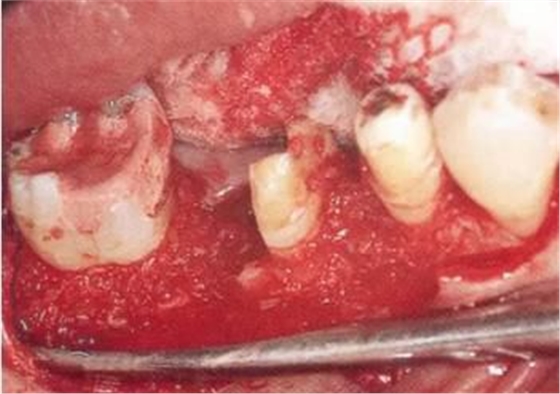

▲圖11-5

右下6進(jìn)行牙半切除并將遠(yuǎn)中牙根拔除。右下5,7的骨組織缺損部位進(jìn)行骨組織移植,以及在右下7進(jìn)行GTR(wraparound)。